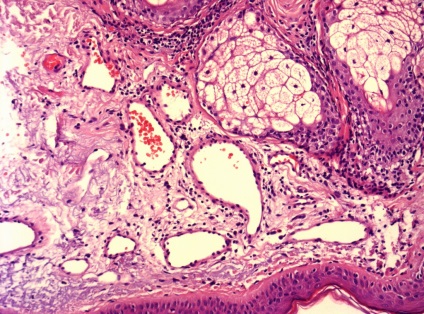

Ma már többféle bőr biopszia, köztük - tűbiopszia, excisional biopszia és derma biopszia. Dermatomális és excíziós bőr-biopszia végre az „akut” vagy „nyitott” módon. Amikor egy szikével biopszia dermatomális felületi réteg a bőr, míg a excisional biopszia - kivágtuk nagyobb bőrterületet, majd varrókészülék (fénykép 1). Ugyanezt a technikát használunk, és ha a biopszia musculocutaneous csapóajtót, ha egyidejűleg kimetszett bőr, a bőr alatti szövet és izom lebeny alá.

Ábra. 4 Skin tumorképződés - jelzi excisiós biopszia

Ábra. 5 érelváltozások a bőr - egy jelzés a biopszia dermatomá

Ábra. 6,7,8 érelváltozások a bőr - jelzi biopszia a bőr graft

Következtetés (patológus MD Karev VE): egy jóindulatú daganat tömegének faggyúmirigy; haemangiomatosis bőrben, cutan vasculitis (gyulladásos elváltozások érfalak).